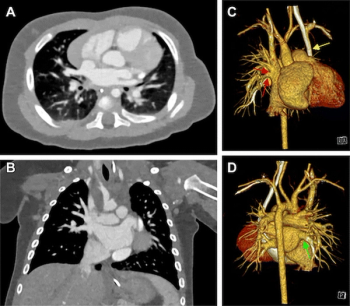

Photon-counting computed tomography (PCCT) significantly increased the signal-to-noise ratio (SNR) and the contrast-to-noise ratio (CNR) in comparison to dual-source CT (DSCT) at similar radiation dosing, according to a new study of over 100 children with suspected congenital heart defects.